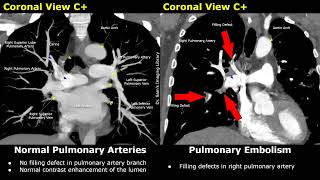

CT Angiography Normal Vs Pulmonary Embolism | Polo Mint, Railway Track Signs | Acute & Chronic Types

2025-11-02

en